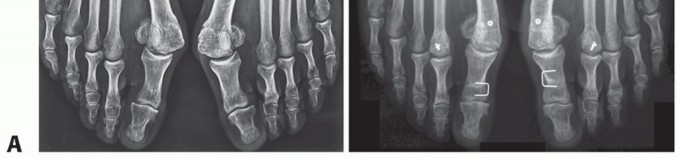

FIG 3 • A. AP radiograph from a patient with juvenile hallux valgus in which the absolute congruence of the MTP joint can be noted. The misalignment of the distal articular surface of the metatarsal determines the hallux valgus deformity. B. Both edges of the metatarsal head articular surface are marked. The DMAA is measured between the line that connects the articular edges and the perpendicular to the diaphyseal axis of the first metatarsal. The normal value is up to 8 degrees.

In our experience, the procedure reliably and reproducibly corrects the 1-2 IMA, HVA, and increased DMAA (FIG 5) and can be useful as a complementary procedure in severe cases (FIG 6).

FIG 5 • A. Preoperative and postoperative radiographic images of a right foot with hallux valgus with increased DMAA, treated by the biplanar chevron osteotomy. The correction of the DMAA and the sesamoid position is easy to see. The valgus of the great toe was also satisfactorily corrected. B. In these images, we can see the correction obtained with the biplanar distal chevron osteotomy. The cephalic fragment was 6 mm laterally dislocated to correct the IMA and the sesamoid position. The DMAA and HVA were corrected to normal values. In the lateral view, we can see the size and position of the screw used in the fragment fixation. C. Lateral views of a patient treated by the biplanar distal chevron osteotomy, where we can see both the plantar and dorsal arms of the osteotomy, the position of the screw used in its fixation, and the alignment of the cephalic fragment with the metatarsal diaphysis resulting from the dorsal fragment resection.

FIG 6 • Preoperative (A) and postoperative (B) radiographic images of a patient with severe hallux valgus

deformity with increased DMAA treated by the combination of a proximal opening wedge osteotomy, a distal

biplanar chevron osteotomy, and a proximal phalangeal closing wedge “Akin” osteotomy.